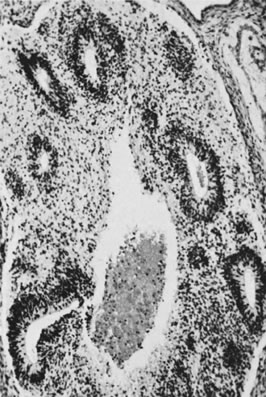

This tumor, which was originally called endodermal sinus tumor, is characterized by a variety of patterns and cell types that have been interpreted as simulating those of yolk sac epithelium and its derivatives.43,44 The neoplasm accounts for approximately 20% of primitive germ cell tumors of the ovary. The endodermal sinus tumor is the first described and the most common subtype of yolk sac tumor. It is characterized by a network of spaces lined by immature epithelial cells (reticular pattern) and occupied focally by single papillary projections, which have been designated Schiller-Duval bodies (Fig. 18). These structures, which contain single central blood vessels and are lined by neoplastic epithelium, resemble to some extent downgrowths of yolk sac epithelium into the extraembryonic mesenchyme of the labyrinthine placenta of the rodent, known as endodermalsinuses. Schiller-Duval bodies are present in most endodermal sinus tumors but may be rare or absent; in such cases, the tumor may have a pure reticular pattern, which merges in many cases with microcystic foci. Another microscopic feature of the endodermal sinus tumor is the presence of intracellular hyaline bodies (Fig. 19). The yolk sac nature of the tumor is confirmed by the immunohistochemical demonstration of alpha-fetoprotein in some of the tumor cells and by the presence of elevated levels of this oncofetal protein in the serum. A more mature form of yolk sac tumor is characterized by a polyvesicular vitelline pattern, in which vesicles lined by columnar-to-flattened epithelium are present in a cellular stroma. These vesicles often show an eccentric constriction, which has been interpreted as a recapitulation of the formation of the secondary or definitive yolk sac from the primary yolk sac (Fig. 20). In the normal embryo, the primary yolk sac becomes vestigial, and the secondary yolk sac develops into the gastrointestinal tract and its appendages, such as the liver. The polyvesicular vitelline pattern is usually a minor component of a yolk sac tumor, but in rare cases, it predominates. Other patterns are papillary and solid. In addition, in keeping with the role of the yolk sac in the formation of the gastrointestinal tract and its appendages, rare yolk sac tumors have a distinctive glandular pattern with cribriform areas and are composed of cells that resemble those of the primitive intestinal tract. These tumors are called glandular yolk sac tumors45; some of them simulate closely endometrioid adenocarcinomas with or without squamous differentiation (endometrioid-like yolk sac tumors) and can be distinguished from true endometrioid tumors by the demonstration of alpha-fetoprotein in the cytoplasm of their neoplastic cells.46 A final form of yolk sac tumor is the hepatoid form, which is indistinguishable from a hepatocellular carcinoma of the liver and is also associated with alpha-fetoprotein production.47 Gross examination of a yolk sac tumor reveals a solid mass that typically shows areas of necrosis, gelatinous degeneration, hemorrhage, and often cyst formation (Fig. 21). Rupture has been reported in approximately one third of cases.

Fig. 20. Endodermal sinus tumor, polyvesicular vitelline pattern (magnification, ×190). Secondary yolk sac at right is budding from larger primary yolk sac.(Serov SF, Scully RE, Sobin LH: Histological Typing of Ovarian Tumours. Geneva, World Health Organization, 1973.)